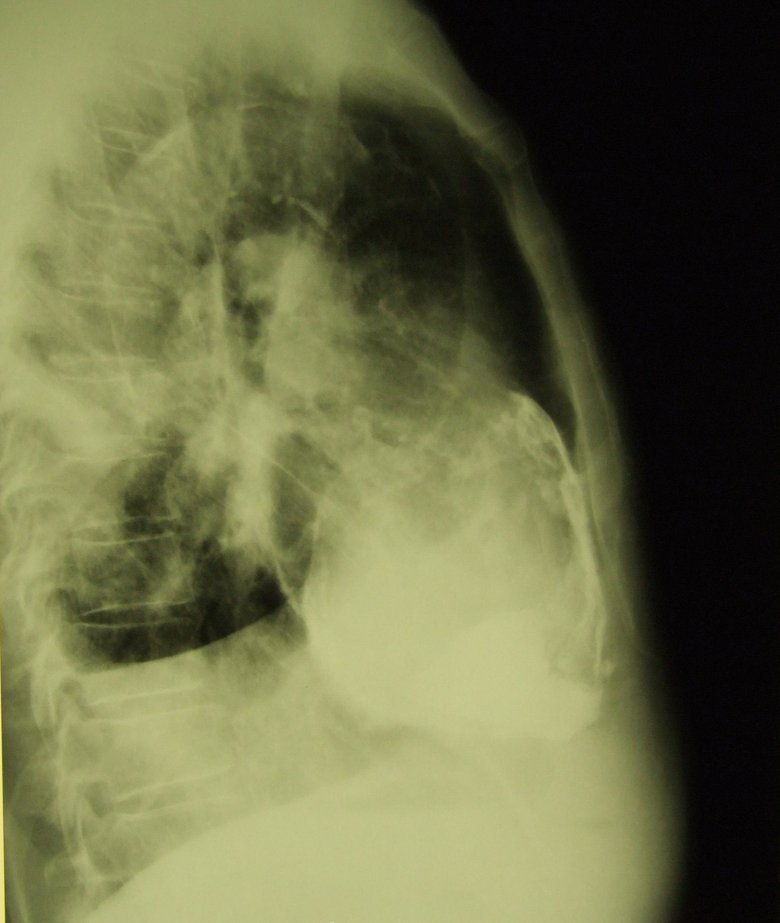

Панцирное сердце

Обсуждалось здесь viewtopic.php?f=24&t=860